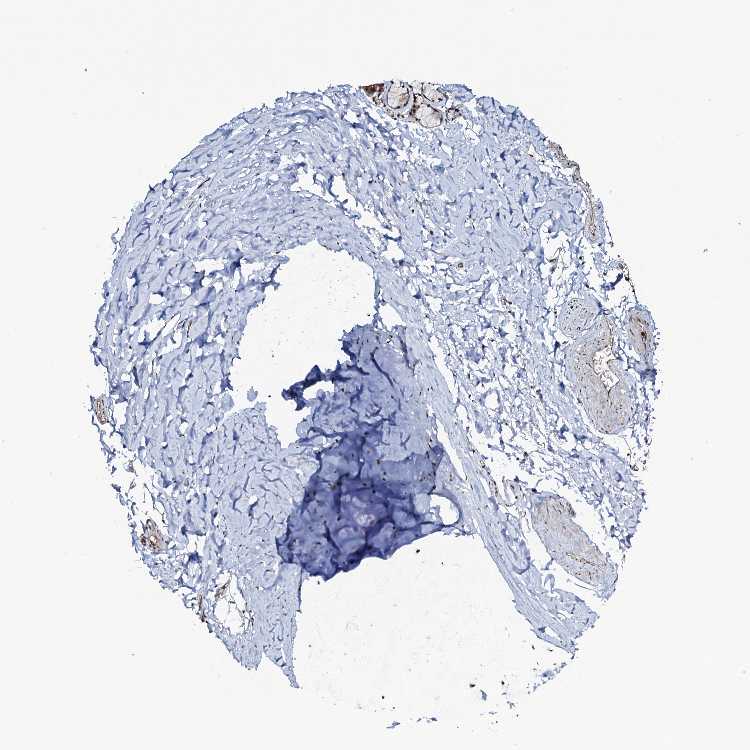

ADIPOSE TISSUE - Antibody stainingi

Antibody staining in the annotated cell types in the current human tissue is reported as not detected, low, medium, or high, based on conventional immunohistochemistry profiling in selected tissues. This score is based on the combination of the staining intensity and fraction of stained cells.

Each image is clickable and will lead to virtual microscopy that enables deeper exploration of all samples and also displays staining intensity scores, fraction scores and subcellular localization as well as patient and tissue information for each sample.

Antibody HPA040410Antibody HPA040441

Adipocytes Not detectedNot detected